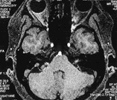

面肌痙攣(Hemifacial Spasm,HFS),又稱面肌抽搐,可以分為兩種,一種是原發(fā)性面肌痙攣,一種是繼發(fā)性面肌痙攣,即面癱后遺癥產(chǎn)...【詳細】